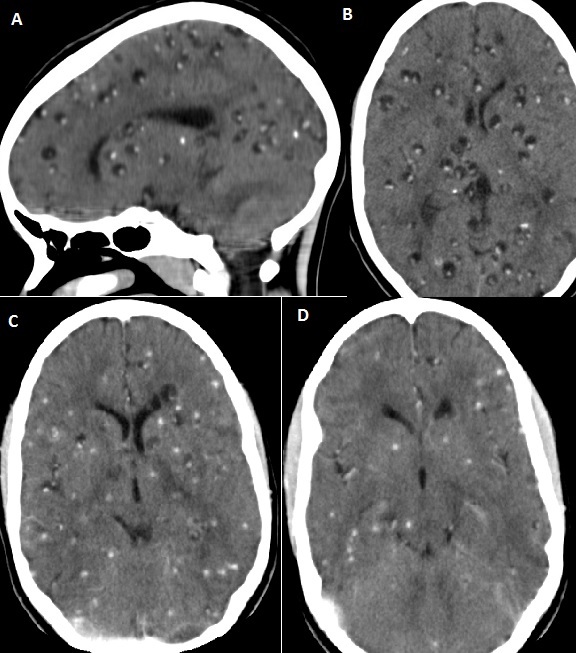

Standard adult head phantom with brain parenchyma, CSF, skull, and ventricles